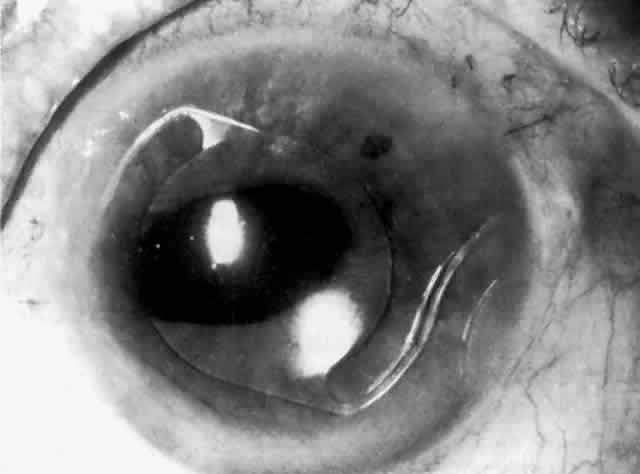

MANAGEMENT. Laser peripheral iridectomy quickly resolves pupillary block (Figs. 6 and 7). Because of inflammation and iridocorneal contact peripherally, this procedure may be difficult to accomplish. If the view is inadequate or a laser is not available, pupillary dilation with phenylephrine will in some cases relieve pupillary block (Figs. 8 and 9). Ultimately the patient will need a laser peripheral iridectomy. If peripheral anterior synechiae have formed or the IOP elevation persists after relief of the pupillary block, the patient will require management similar to that used in chronic angle-closure glaucoma.

Fig. 6. Pupillary block with iris bombé around haptics of anterior chamber lens implant, resulting in elevated intraocular pressure.

Fig. 7. Resolution of pupillary block after laser peripheral iridectomy.

Fig. 8. Iris bombé nasal to anterior chamber lens implant before dilation (shadowed area on right). No peripheral iridectomy is present.

Fig. 9. Resolution of pupillary block and iris bombé after pupillary dilation. A subsequent laser peripheral iridectomy was performed.